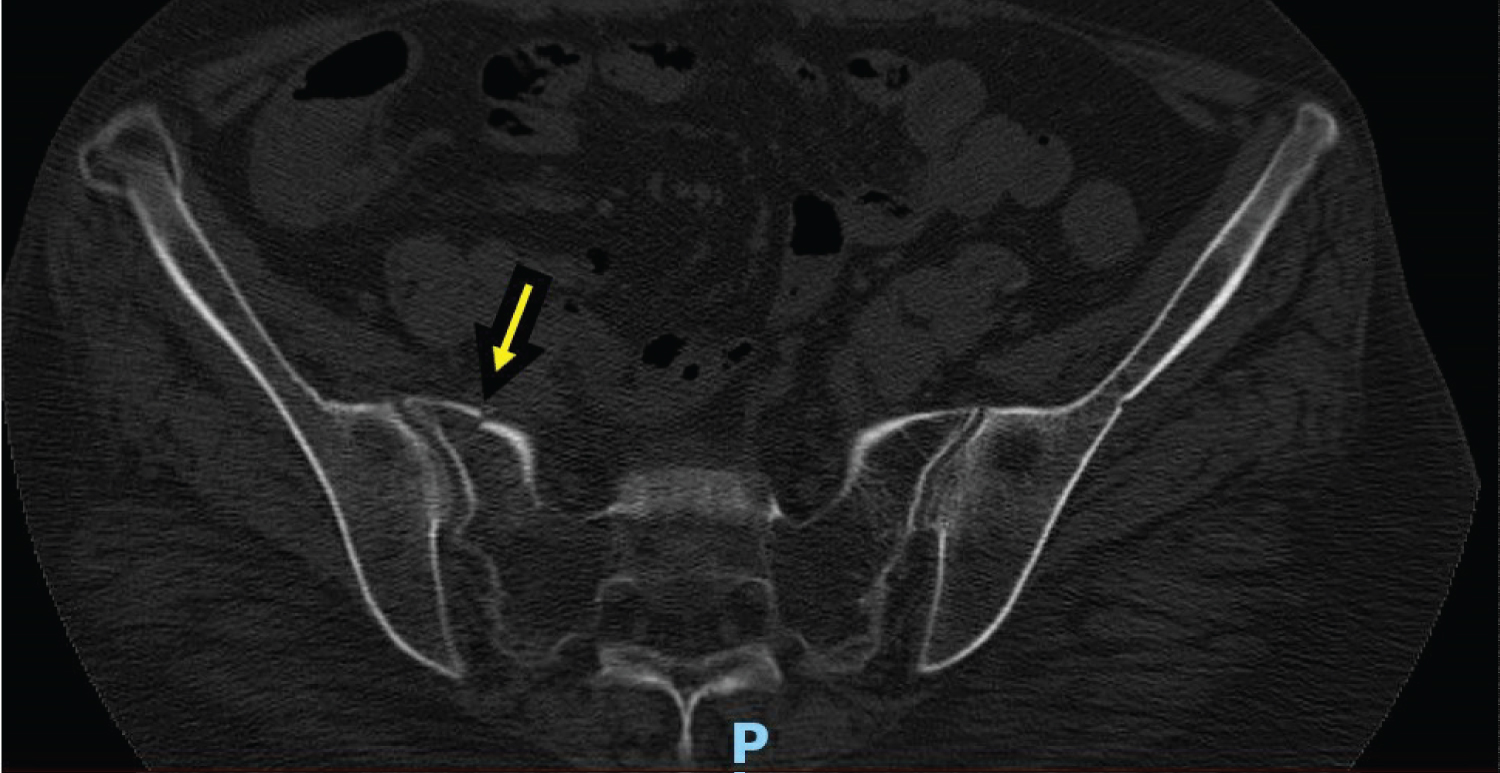

A 54-year-old African American Female presented to the ED reporting a fall after slipping on water with initial CT images of her pelvis showing a minimally displaced right sacral fracture (Figure 1 and Figure 2). The right anterior superior iliac spine changes seen on CT were previously noted on imaging from a different hospitalization. She had both an elevated Creatine Kinase (CK) (2758 U/L) and AST (411 IU/L) level. The patient was admitted for observation for 24 hours to have Orthopedic Surgery further evaluate the imaging and quality of the fracture. On further questioning of the patient, she mentioned multiple falls over the past 1-2 years requiring ED visits for fractures of various regions of her body including: right radius, left ankle, and multiple left ribs (sixth-ninth and eleventh). She reported an associated generalized weakness throughout her body, especially of her lower extremities which would lead to the falls. She reports these episodes of weakness are accompanied by pain, last for 1-2 weeks, and then self-resolve. She has noticed these episodes with stress and most recently, after a heated disagreement with a family member. On initial examination of the patient, in addition to sacral pain, she had a slightly erythematous rash around her eyes (images not available), hypopigmentation of her digits and toes, with reddish-violet colored patches over her knees (images not available), as well as macules over her metacarpophalangeal (MCP) and proximal interphalangeal (PIP) joints (Figure 3a, Figure 3b, Figure 3c and Figure 3d).

Figure 2: CT pelvis w/o contrast [Transverse View] - Inferior right pelvis partially displaced fracture 2 of 2. View Figure 2